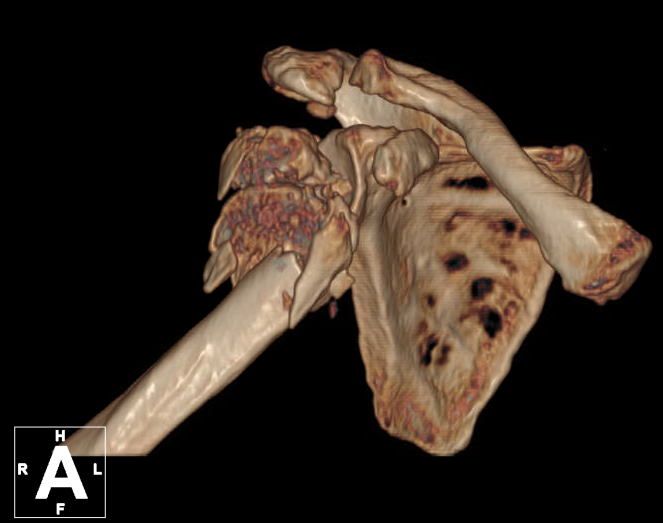

术前肱骨头CT

1、右肱骨近端骨折(Neer 4部分)